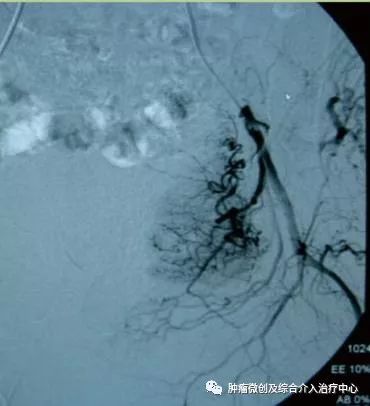

( DSA造影提示胃十二指肠分支血管出血)